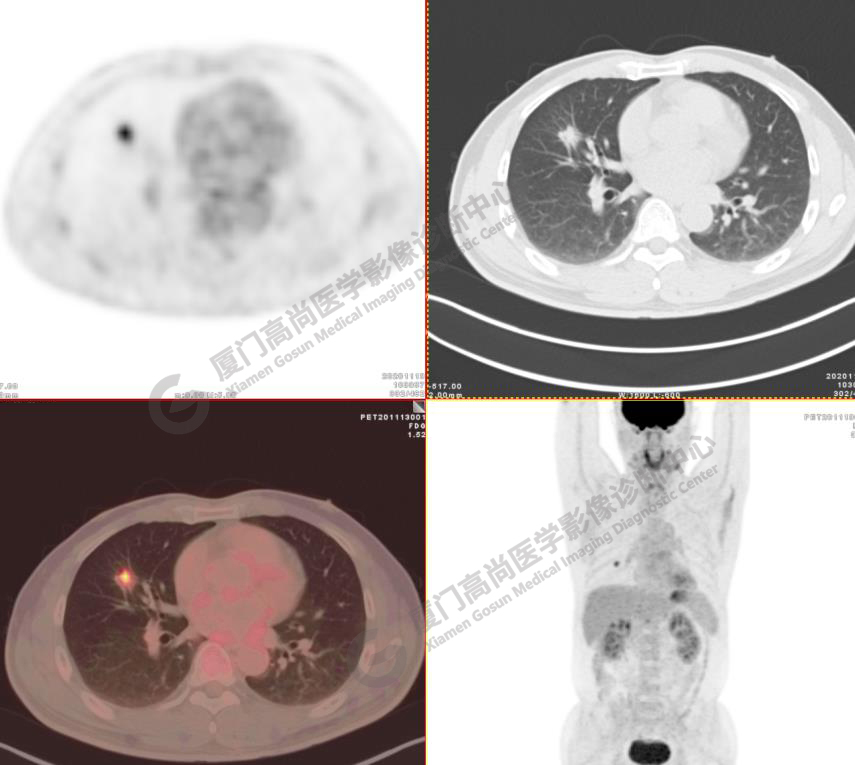

病例1:某男士,52歲,2020年11月體檢,CT發(fā)現(xiàn)右肺中葉結(jié)節(jié)影,查血腫瘤標記物正常。

右肺中葉見一混雜密度磨玻璃結(jié)節(jié),大小約1.8x1.5cm,密度不均勻,以實性密度為主,邊緣可見分葉、毛刺,水平裂牽拉凹陷,F(xiàn)DG攝取增高,SUVmax4.7,肺門、縱隔未見FDG高攝取淋巴結(jié), 未見遠處轉(zhuǎn)移征象。

影像診斷:右肺中葉浸潤性腺癌。(TNM分期 T1bN0M0 ⅠA2期)

病理診斷:浸潤性腺癌